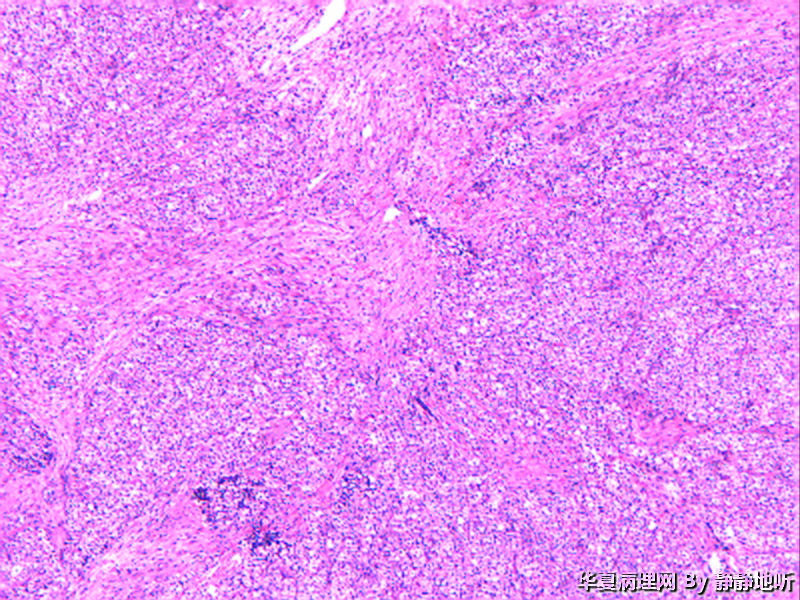

• 骶韧带肿物图2

图2

女性 52岁,盆腔骶韧带肿物。肿瘤球形,直径约2.5厘米,表面光滑,切面结节状,灰粉色。镜下见大量上皮细胞巢,间质为平滑肌。免疫组化:Vimentin +   SMA梭形细胞+  EMA-   CD10-

上级医院做免疫组化:CK+ EMA+  Vimentin +  s-100 弱+  p63-   SMA血管+    CD34 血管+  HMB-45 +  Melanoma+   desmin +   ki-67约20%

会诊意见:低度恶性PEComa